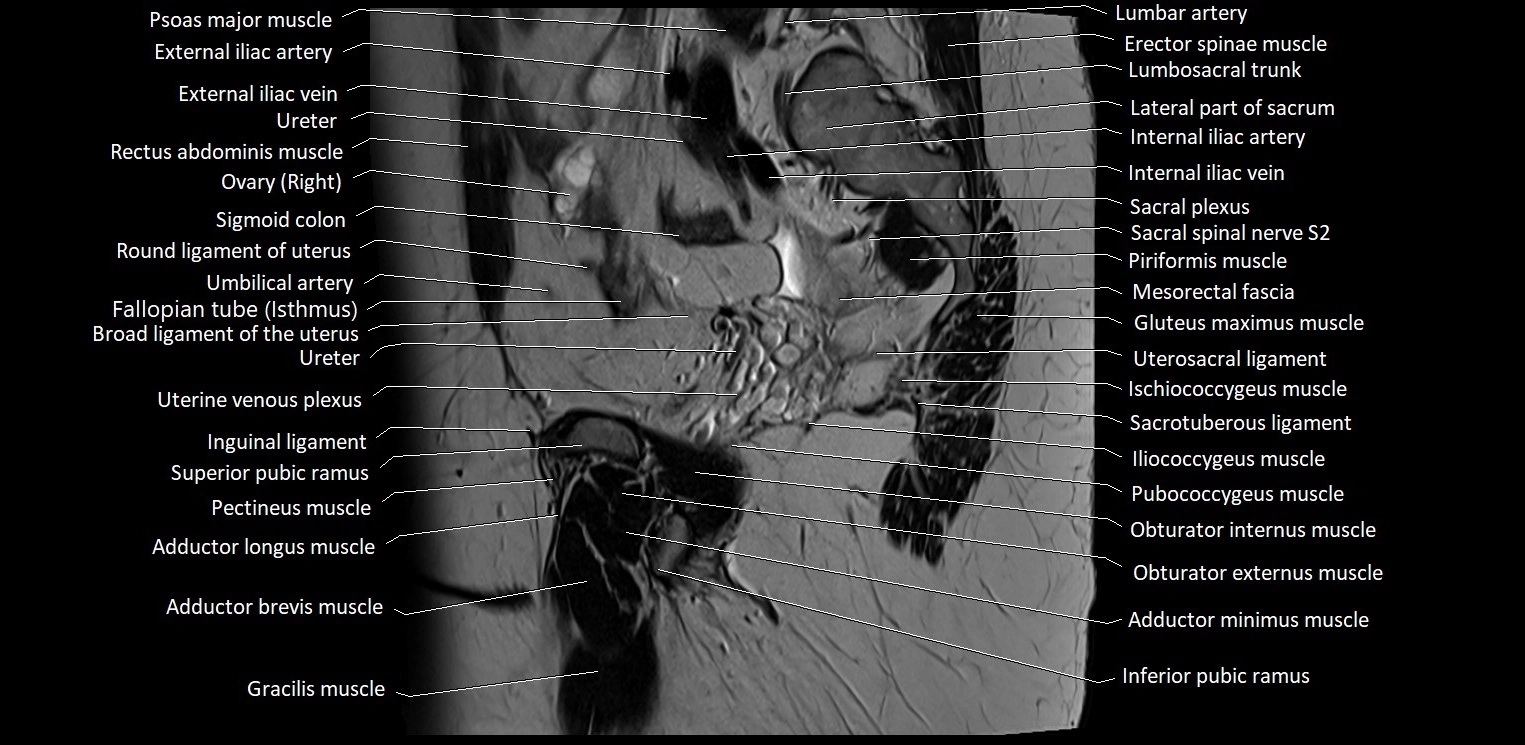

- Psoas major muscle

- External iliac artery

- External iliac vein

- Internal iliac artery

- Internal iliac vein

- Right ovary

- Broad ligament of uterus

- Fallopian tube

- Uterosacral ligament

- Iliococcygeus muscle

- Obturator internus muscle

- Obturator externus muscle

- Gracilis muscle